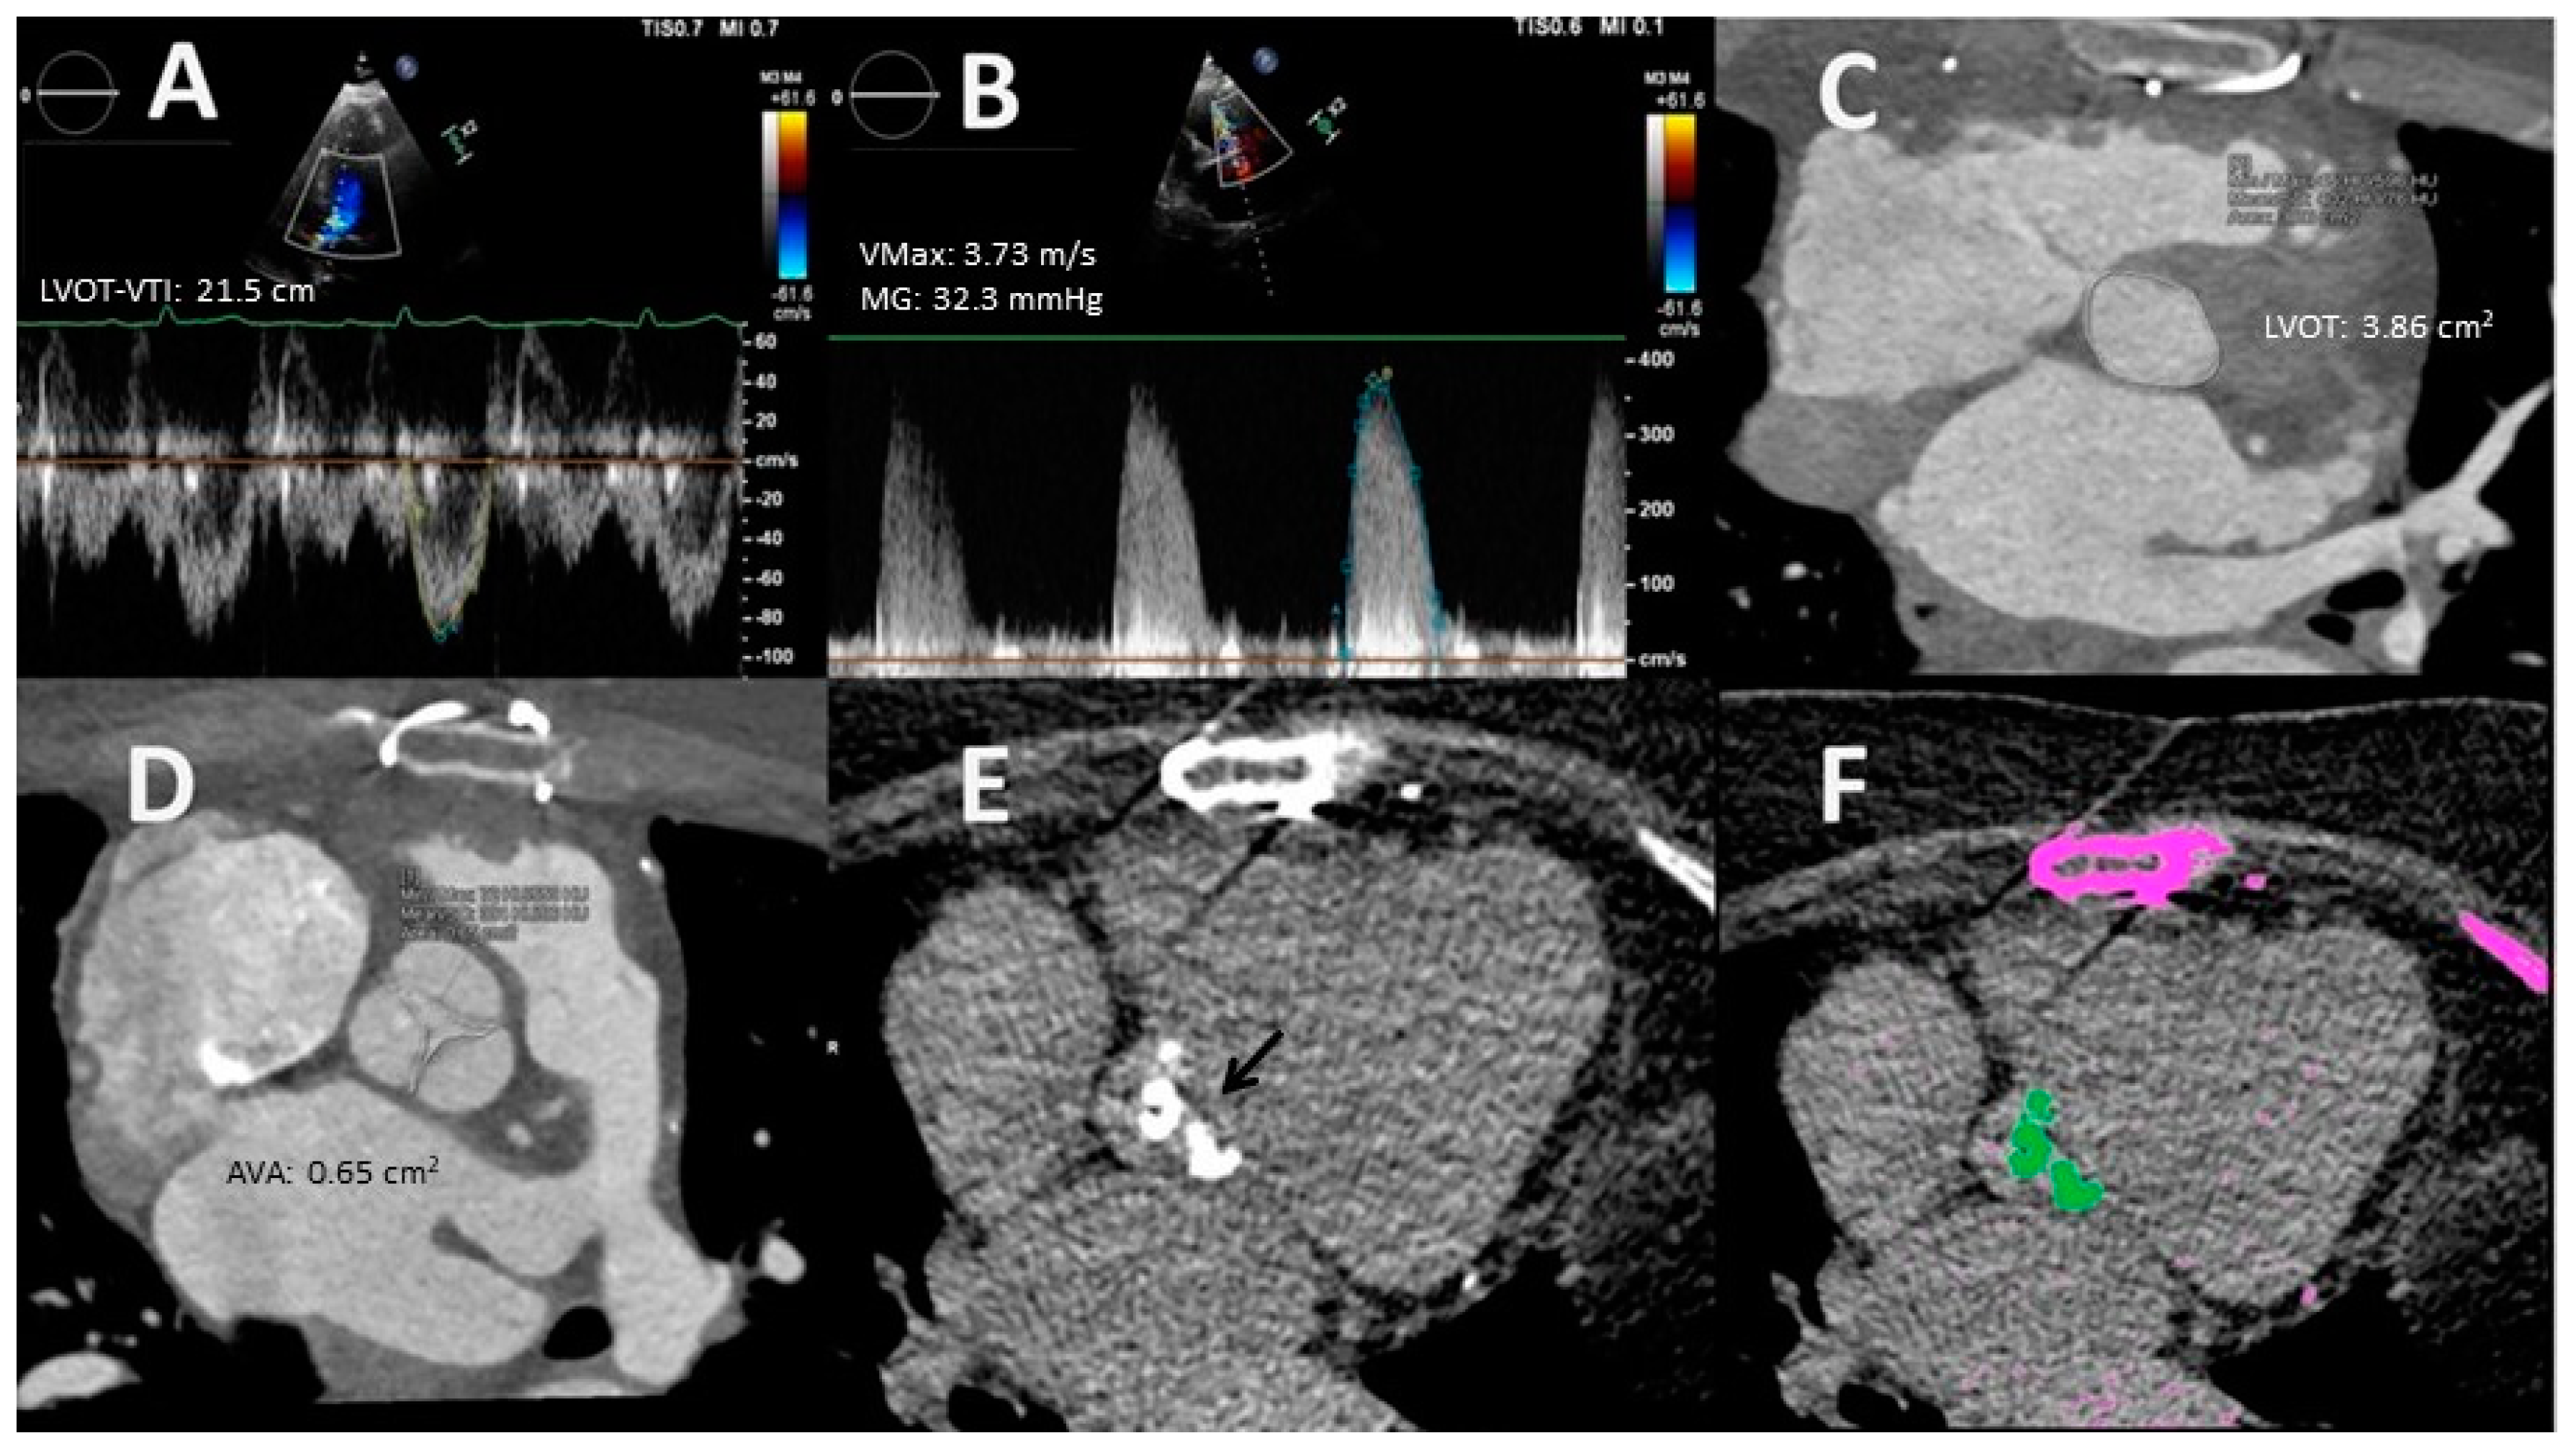

- Planimetry. MDCT allows 3D acquisition throughout the entire cardiac cycle using retrospective protocols. Through multislice reconstructions, planimetry of the AV orifice is feasible. Such a measure has shown good agreement with AVA estimated through the CEq [40]. Concerning LVOT size, MDCT assessment is considered to be the gold standard test [23]. Clavel et al. [41] observed that AVA calculated with a hybrid TTE–MDCT method in which the LVOT area used in the Ceq was obtained with MDCT predicted long-term survival with an optimal cut-off value of 1.2 cm2 instead of 1 cm2 [41].

- Pre-interventional study. Coverage of MDCT at acquisition can be extended to the ascending aorta to measure its diameter and determine the presence of calcifications. This information is helpful in cases where surgical valve replacement is considered. Regarding transcatheter aortic valve replacement (TAVR), CT is the reference technique for procedural planning. MDCT allows a precise estimation of the valve annulus size, its distance to the coronary ostia, and the caliber of the peripheral arterial vascular accesses. All of these parameters are essential to determine the candidacy for TAVR and to select the type and size of the prosthesis. Moreover, the incorporation of coronary assessment into CT protocols does not require an increase in contrast or radiation doses and has been shown to reduce the need for invasive coronary angiography in a noteworthy percentage of cases [42]. The use of the novel CT-derived fractional flow reserve technique is still not recommended because it may increase the number of false positive tests [43].

- Inter- and intraobserver reproducibility for LVOT diameter measurements is the main source of inaccuracy relative to the CEq. Although variability in such measurements is only ≈5 ± 4% and ≈3 ± 2%, respectively [21], it may be meaningful because this parameter is squared in CEq.

- Three-dimensional (3D) TTE acquisition: a 3D echo dataset allows direct LVOT measurement by multiplanar reformat, in a similar way MDCT does, avoiding geometrical assumptions. LVOT assessment by 3D TTE is more reproducible than 2D TTE and can be employed in the CEq (“ellipsis formula”) [23,28]. Three-dimensional probes are not available in many centers and, despite recent technological advances, the spatial and temporal resolution of 3D TTE is low, so its role may still be limited.